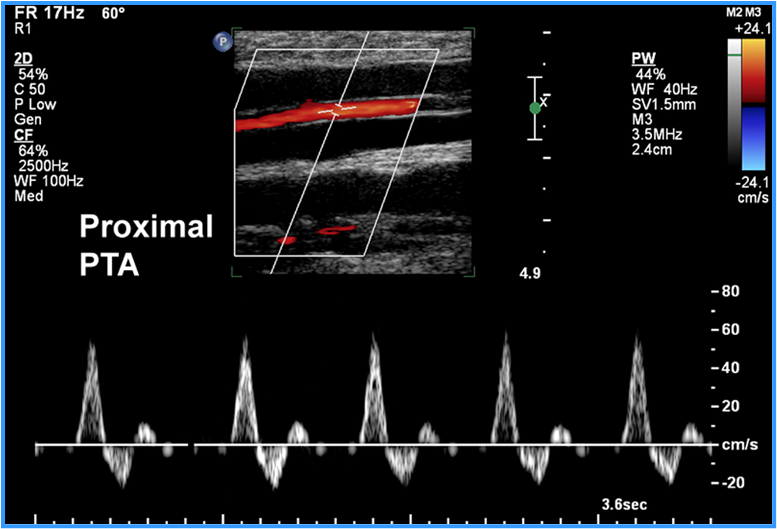

proximal PTA spectral US